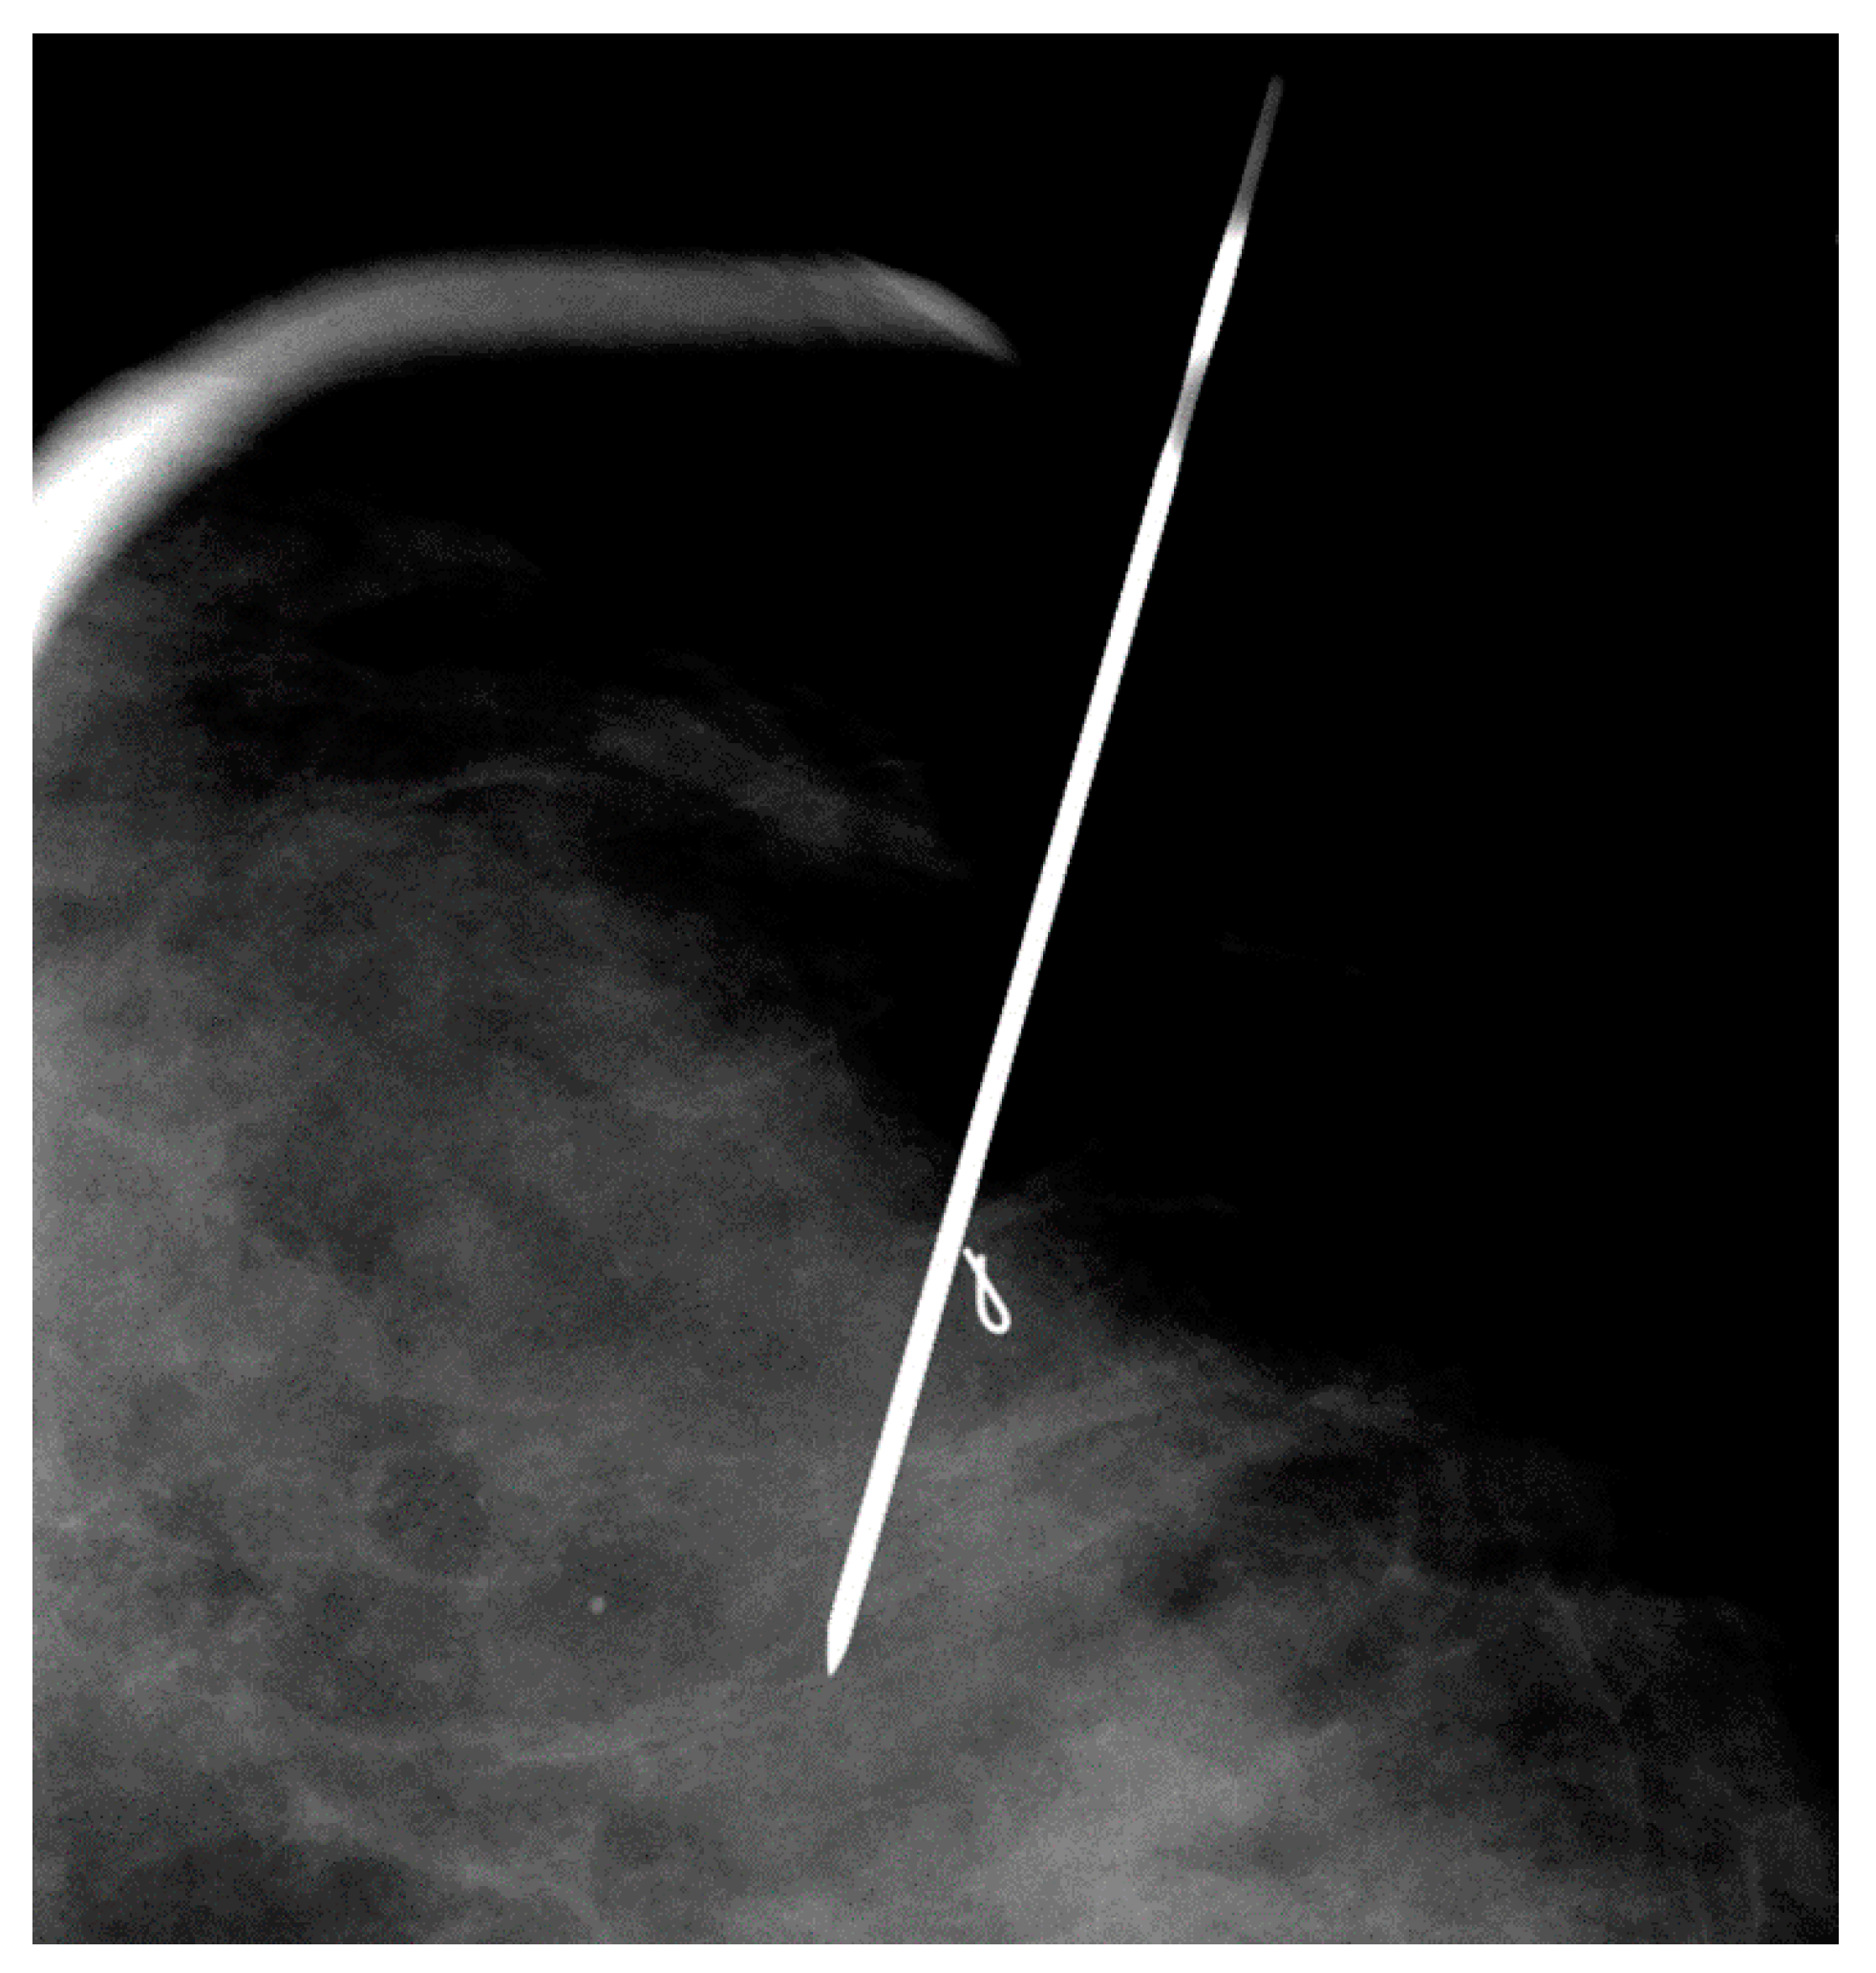

Two tuberculin syringes are added to the standard procedure tray (Figure 4) for mammographically-guided SLNB. The radiopharmaceutical is kept in a lead container until the time of injection. Four mL of Tc-99m-sulfur colloid is injected in divided doses through the localizing needles (Figure 5). Hawkins, Homer, spinal (Figure 6) and Kopans needles have been used for mammographically–guided SLNB. After the injection of Tc-99m-sulfur colloid, saline is injected through tuberculin syringes to flush the localization needles (Figure 7).

Figure 6. Mammographically-guided SLNB with two spinal needles.

Figure 8. Mammographically-guided SLNB with one needle, targeting a clip marker.